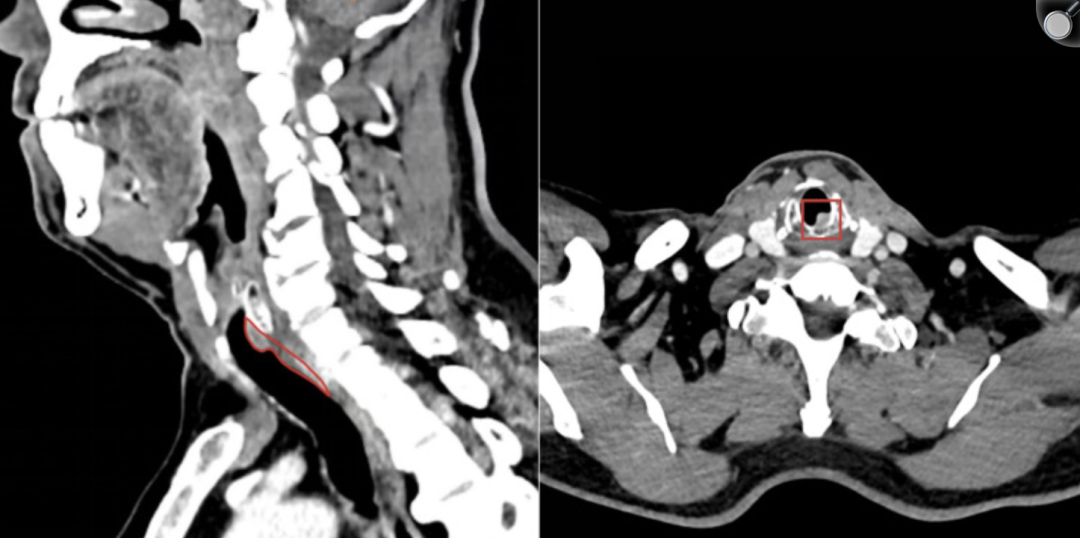

目前,在已有的气道蚂蟥寄生病例报告中,虫体长度通常在 4~5cm 之间。2024 年 10 月,云南省肿瘤医院同样报告了一例 8cm 的气管蚂蟥,蚂蟥位于声门下气管后壁,CT 上最初被误诊为气管内肿瘤。

云南省肿瘤医院病例报告图片(图源:参考资料 4)